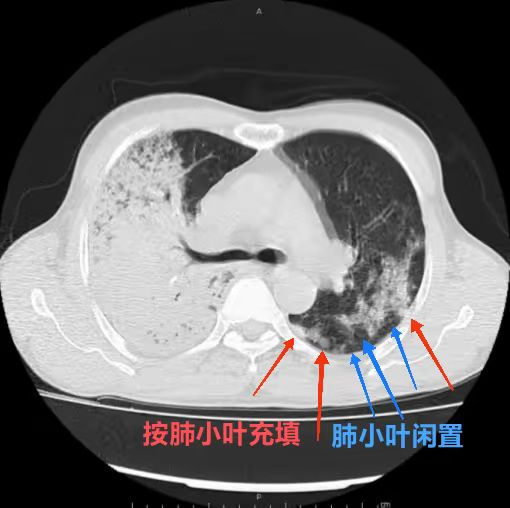

3.  小病灶(血管炎)是否有小叶充填及闲置?

肺炎链球菌肺炎多为肺泡性肺炎,少数血播肺炎链球菌肺炎好发于老年人及免疫力低下人群,PCT 明显增高。影像上,早期在血管炎的基础上仍能见到按肺小叶充填及闲置的表现(肺泡性肺炎的表现),而大片实变影已不能分辨是否为血管炎(病灶边缘磨玻璃仍可看出血管炎),在肺尖段不会占据整个层面(与铜绿假单胞菌肺炎不同),而在下肺往往表现为齐头并进的特点,分布上多上肺优势。